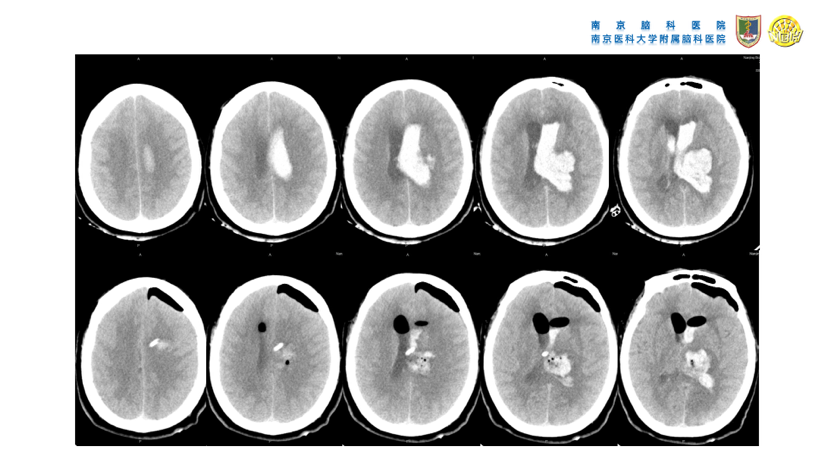

高血压性脑出血的微创手术治疗(高血压性脑出血的血压管理、镇静镇痛处理、手术指征、手术方法等重要问题)